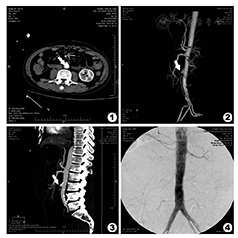

患者,男,64岁,因"便血3 d"入院。患者于2014年3月29日进食后突感腹胀、恶心、呕吐胃内容物1次,呈深褐色,无鲜血。随即排鲜血样便500 ml,伴头晕、乏力。遂至当地医院就诊,大便常规隐血4+,予制酸剂等药物止血治疗效果不佳,仍有便血。遂转本院急诊,血常规:白细胞9.4×109/L;血红蛋白94 g/L;血小板164×109/L,全腹CT平扫未见明显异常改变,拟诊"消化道出血"于2014年4月1日收住消化内科。入院体格检查:T 37.6℃;P 79次/min;R 21次/min;BP 114/54 mmHg(1 mmHg=0.133 kPa);神志清楚,轻度贫血貌,全身浅表淋巴结未扪及肿大,双巩膜无黄染,心肺(-),腹软,无压痛反跳痛,腹部未扪及搏动性包块,无血管杂音,肠鸣音轻度活跃。初步诊断:消化道出血(消化道肿瘤?消化道血管畸形?炎症性肠病?)。既往有吸烟史,1包/d,30多年,未戒。入院后完善内镜检查,胃镜提示:十二指肠球降部糜烂;肠镜:结肠多发毛细血管团。全腹螺旋CT(2014年4月4日):未见明显异常。胶囊内镜检查:小肠血管畸形,予止酸、止血、补液对症支持治疗,患者病情一度稳定。2014年4月9日患者突发剧烈腹痛、反复大量呕血,急诊行床旁胃镜检查,见高位胃体巨大血凝块形成伴活动性出血,血管性病变首先考虑。外科会诊有手术指征。遂于2014年4月11日行"胃切开止血术" ,术中见胃体小弯侧一大小约3 mm溃疡灶,术后转ICU治疗。此后病情稳定,2014年4月13日脱机拔管,但患者2014年4月14日再次呕血、解暗红色血便,量较多。遂行腹腔动脉CT血管造影(CTA)检查:肠系膜上动脉、腹主动脉硬化,腹主动脉右肾下极水平局部囊袋状外突改变,动脉瘤可能;肠系膜上动脉CTA示:肠系膜上动脉壁欠光滑,内未见明显充盈缺损改变,肠管内未见造影剂溢出。见图1,图2,图3。2014年4月16日患者再次消化道大出血,进而出现失血性休克,血压波动在60~70/40~50 mmHg,予继续输血补液抗休克治疗,并联系放射科,行腹主动脉造影检查,术中考虑"腹主动脉瘤局部出血" ,遂予微创覆膜支架一枚行腹主动脉腔内修复术,造影提示支架展开良好,未见出血,腹主动脉血流通畅,见图4。术毕回病房后,患者持续出血,胃管减压在短时间内引流出1 500 ml鲜血,经快速补液补血,血压仍持续下降,遂剖腹探查。术中探查见腹腔内无明显渗夜,胃及肠腔内大量积血,切开胃前壁可见大量鲜血及凝血块,予以清除,见鲜血于十二指肠涌出,术中胃镜探查见十二指肠水平部后壁一活动性出血,胃镜下钛夹止血无效,遂切开十二指肠水平部,止血后见十二指肠外活动性出血,考虑腹主动脉假性动脉瘤十二指肠瘘伴大出血,遂阻断腹主动脉,分离十二指肠和腹主动脉后,见腹主动脉上一0.5 cm×0.5 cm破口,予缝合止血。但术中患者出血大量并发弥漫性血管内凝血(DIC),腹腔及后腹膜广泛渗血,无法止血而死亡。